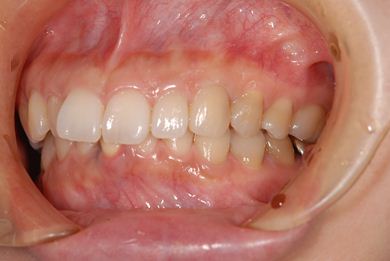

治療後

• 治療後